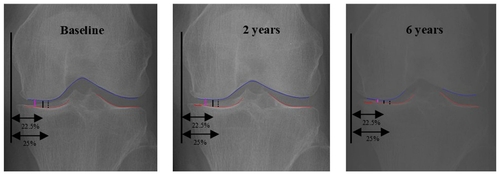

• 연합뉴스"AI로 무릎 골관절염 '최대 마모 지점' 정밀진단"